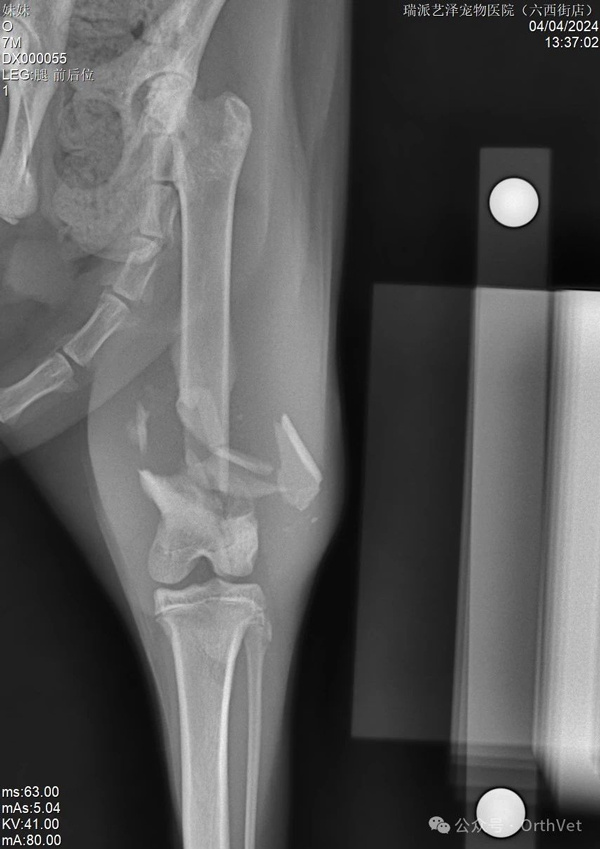

The above are preoperative X-rays